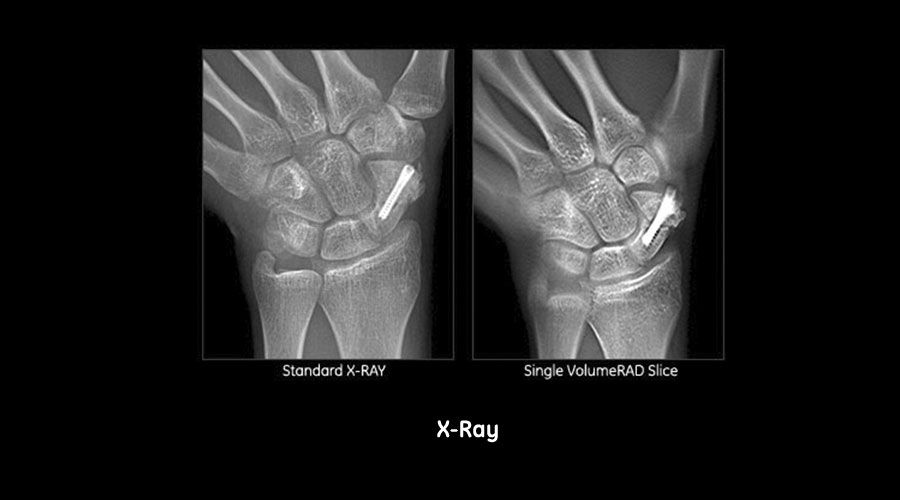

Samir Mehta, M.D.,

Chief of Orthopaedic Trauma & Fracture Service and Assistant Professor of Orthopaedic Surgery at the University of Pennsylvania, presents 2 fracture cases that involve hardware.

"What we can get with advanced imaging is an ability to understand our fracture pattern when it's out of plane. VolumeRAD really does this very well"

David E. Quinn, M.D.,

Board Certified Orthopedic Surgeon at the Capital Region Orthopaedics, Albany, NY, discusses three upper extremity cases.

"As orthopedic surgeons, we're trying answer some very simple questions especially with respect to fracture care ... Is there a problem? Does the patient need an operation or is it indicated? Has it been done properly? Is the problem resolved? I've found that digital tomosynthesis helps answer these questions in a substantial percentage of cases with minimal risk and minimal expense."